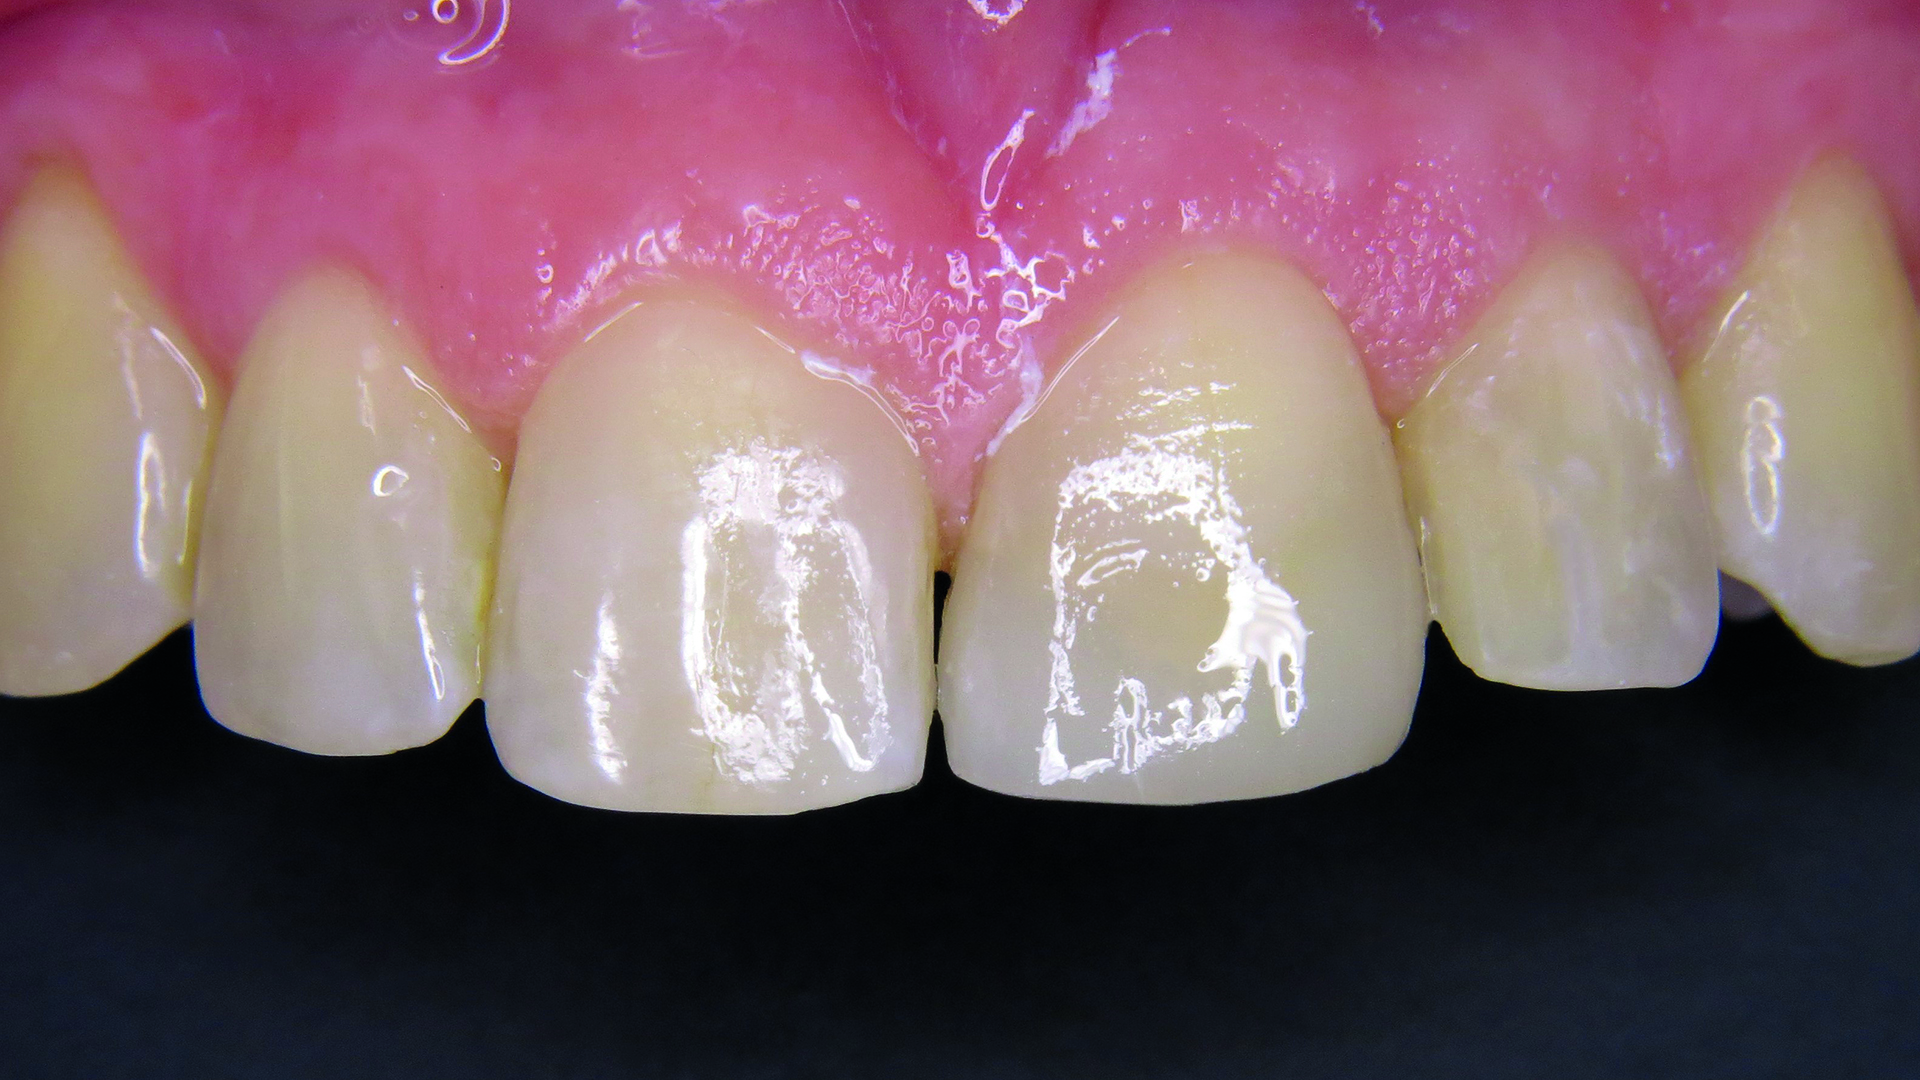

48-letnia pacjentka cierpiąca na alergię wywoływaną przez wiele czynników oraz z historią ataków padaczki w wywiadzie zgłosiła się z życzeniem szybkiego zaplanowania i wykonania estetycznej odbudowy zęba 21, leczonego 10 lat wcześniej (ryc. 1). Zaproponowano pacjentce wykonane analogowo lub cyfrowo uzupełnienie protetyczne lub odbudowę z wykorzystaniem kompozytu opartego na technologii ORMOCER®. Uwzględniając choroby towarzyszące, zdecydowano się zastosować izolację względną. Właściwym dla pacjentki rozwiązaniem okazała się bezpośrednia odbudowa zachowawcza z wykorzystaniem Admira Fusion 5 (VOCO GmbH, Niemcy), gdyż preparat ten nie zawiera klasycznych monomerów. Oczekiwania pacjentki dotyczące estetycznej odbudowy w jak najkrótszym czasie mogły zostać spełnione dzięki wzmocnionemu efektowi kameleona.

Ryc. 1. Pierwotna sytuacja kliniczna – wadliwa rekonstrukcja.

Pacjentka była bardzo zadowolona z uzyskanego efektu (ryc. 13). Przed leczeniem w zębie 21 znajdowało się wadliwe, przebarwione wypełnienie. Ze względu na choroby towarzyszące pacjentki konieczna była szybka i jednocześnie estetyczna odbudowa zęba przedniego, którą uzyskano dzięki zastosowaniu systemu Admira Fusion 5 z wykorzystaniem zaledwie jednego odcienia, bez zastosowania warstw o różnej przezierności. Po wypolerowaniu na wysoki połysk i fluoryzacji preparatem Bifluorid 10 (VOCO GmbH, Niemcy) uzyskano naturalny wygląd rekonstrukcji.

Ryc. 13. Efekt ostateczny – rekonstrukcja wykonana z użyciem Admira Fusion 5.